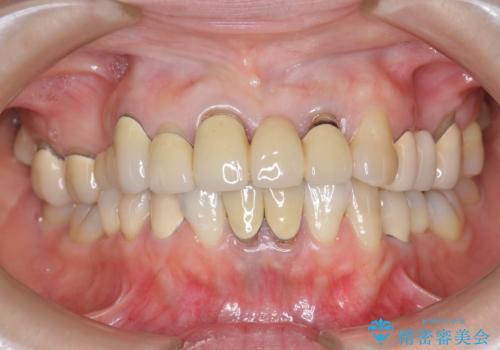

前歯ブリッジのやりかえ

- 前歯の審美障害、見た目の改善を希望され来院されました。

歯肉縁下カリエスも認められるため、挺出を行いセラミックブリッジを審美的に新製します。

- 47万円(仮歯×3・ファイバーコア×2・ジルコニアクラウン×3 歯の挺出)費用は治療当時の料金となります

虫歯が深くなった場合、挺出や歯周外科を行い歯周組織の状態を改善することでより安定した状態で予知性の高いセラミックブリッジを製作することが可能となります。